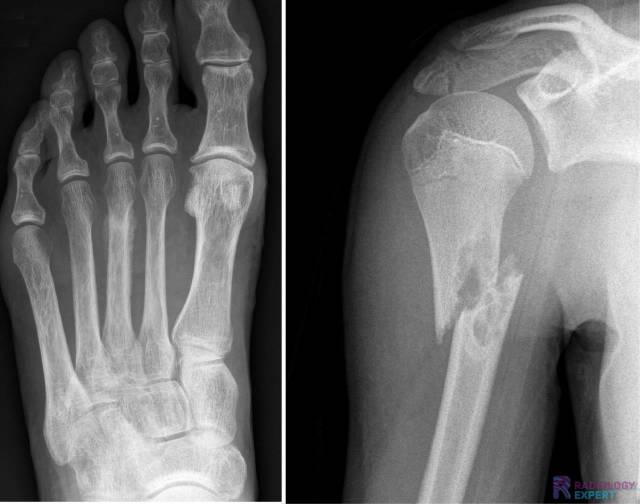

Figuur 1. Laterale en anterior-posterior opname van de linker onderarm/pols. Een kind (9 jaar oud) met distale radiusschacht & ulnaschacht fractuur. Beide tonen een dorso-ulnaire dislocatie over circa een schachtbreedte.